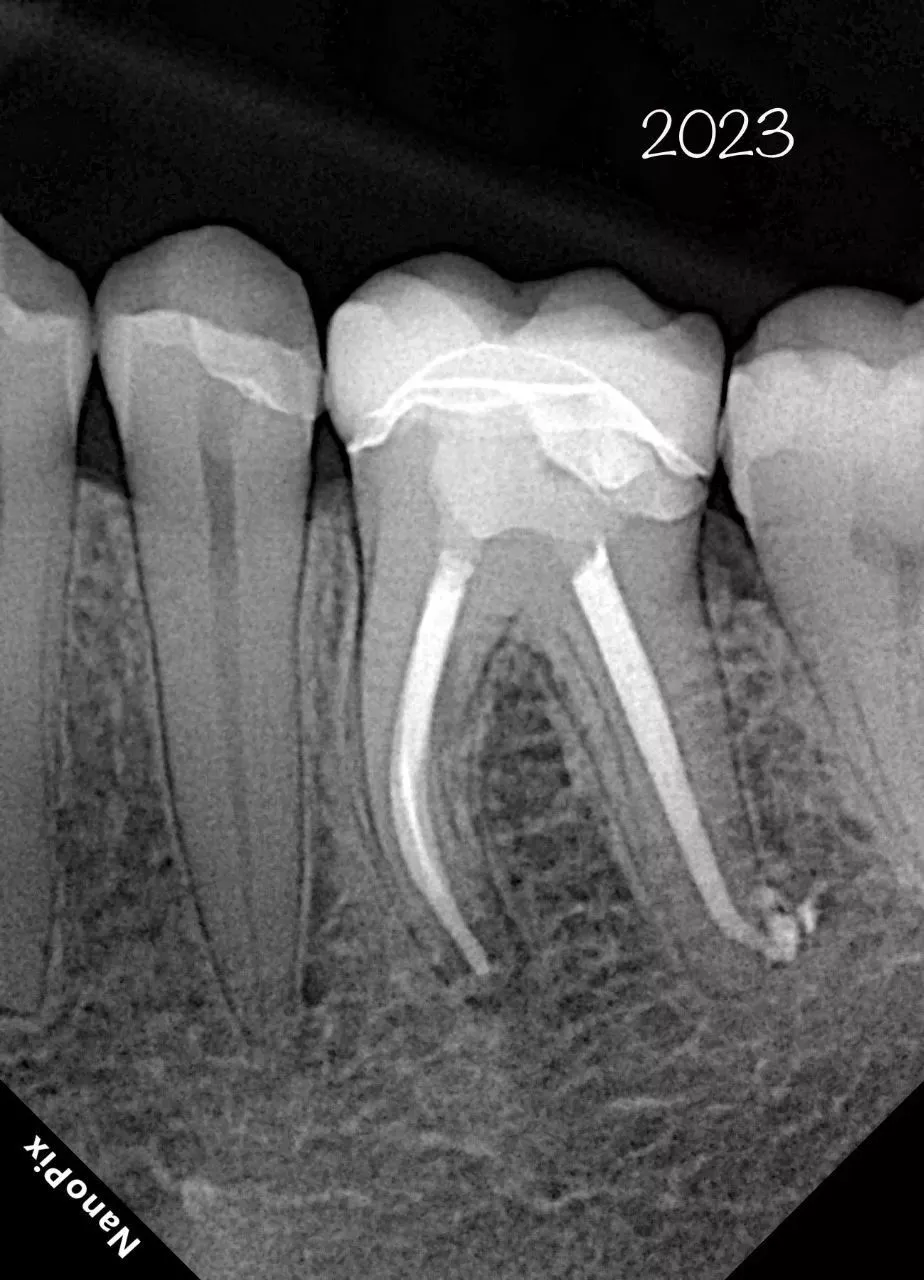

Прибор оснащён высокочувствительным сенсором, с помощью которого устройство фиксирует и передаёт изображение в цифровом виде на компьютер. Принцип работы заключается в следующем: цифровой радиовизиограф размещается в ротовой полости пациента за зубами. С щёчной стороны дентальный рентгеновский аппарат выпускает в направлении радиовизиографа рентгеновские лучи. Лучи, проходя через ткани зуба, фиксируются на радиовизиографе, и полученная информация отображается на экране компьютера. Уникальная технология искусственного интеллекта Nano AI распознаёт зубные патологии, выделяя их цветом и предлагая возможные способы лечения.

- Технология APS CMOS обеспечивает высокое соотношение сигнал/шум и позволяет получать четкие и чистые изображения с максимальной детализацией;

- Технология прямого осаждения CsI позволяет сделать снимок при минимальной безопасной дозе рентгеновского облучения;